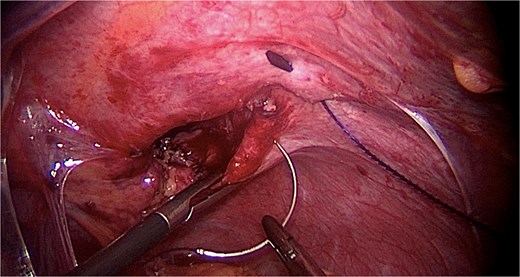

Under general anesthesia, a laparoscopy was made. Intraoperatively, a large diaphragmatic hernia was present with herniation of the omentum (Fig. 3). No transverse colon was found in the hernia, nor were signs of bowel occlusion documented. The content of the hernia was reduced into the peritoneal cavity after performing adhesiolysis and checking organ vitality. The hernia cavity was totally extra-pleural. The parietal pleura was localized cranially, and no expansion was documented even after pulmonary recruitment. The defect in the diaphragm was sutured with PDS 1 go-and-back suture (Stratafix) (Fig. 4) and then covered by a biosynthetic prosthesis (Phasix Mesh), fixed by AbsorbaTack and cyanoacrylate glue (Fig. 5). An intra-abdominal drain was placed. Following the surgery, the patient recovered well and was discharged on the fourth postoperative day (Fig. 6). No postoperative complications occurred. The postoperative imaging control was normal. At the six-month follow-up, the patient showed no signs of recurrence.